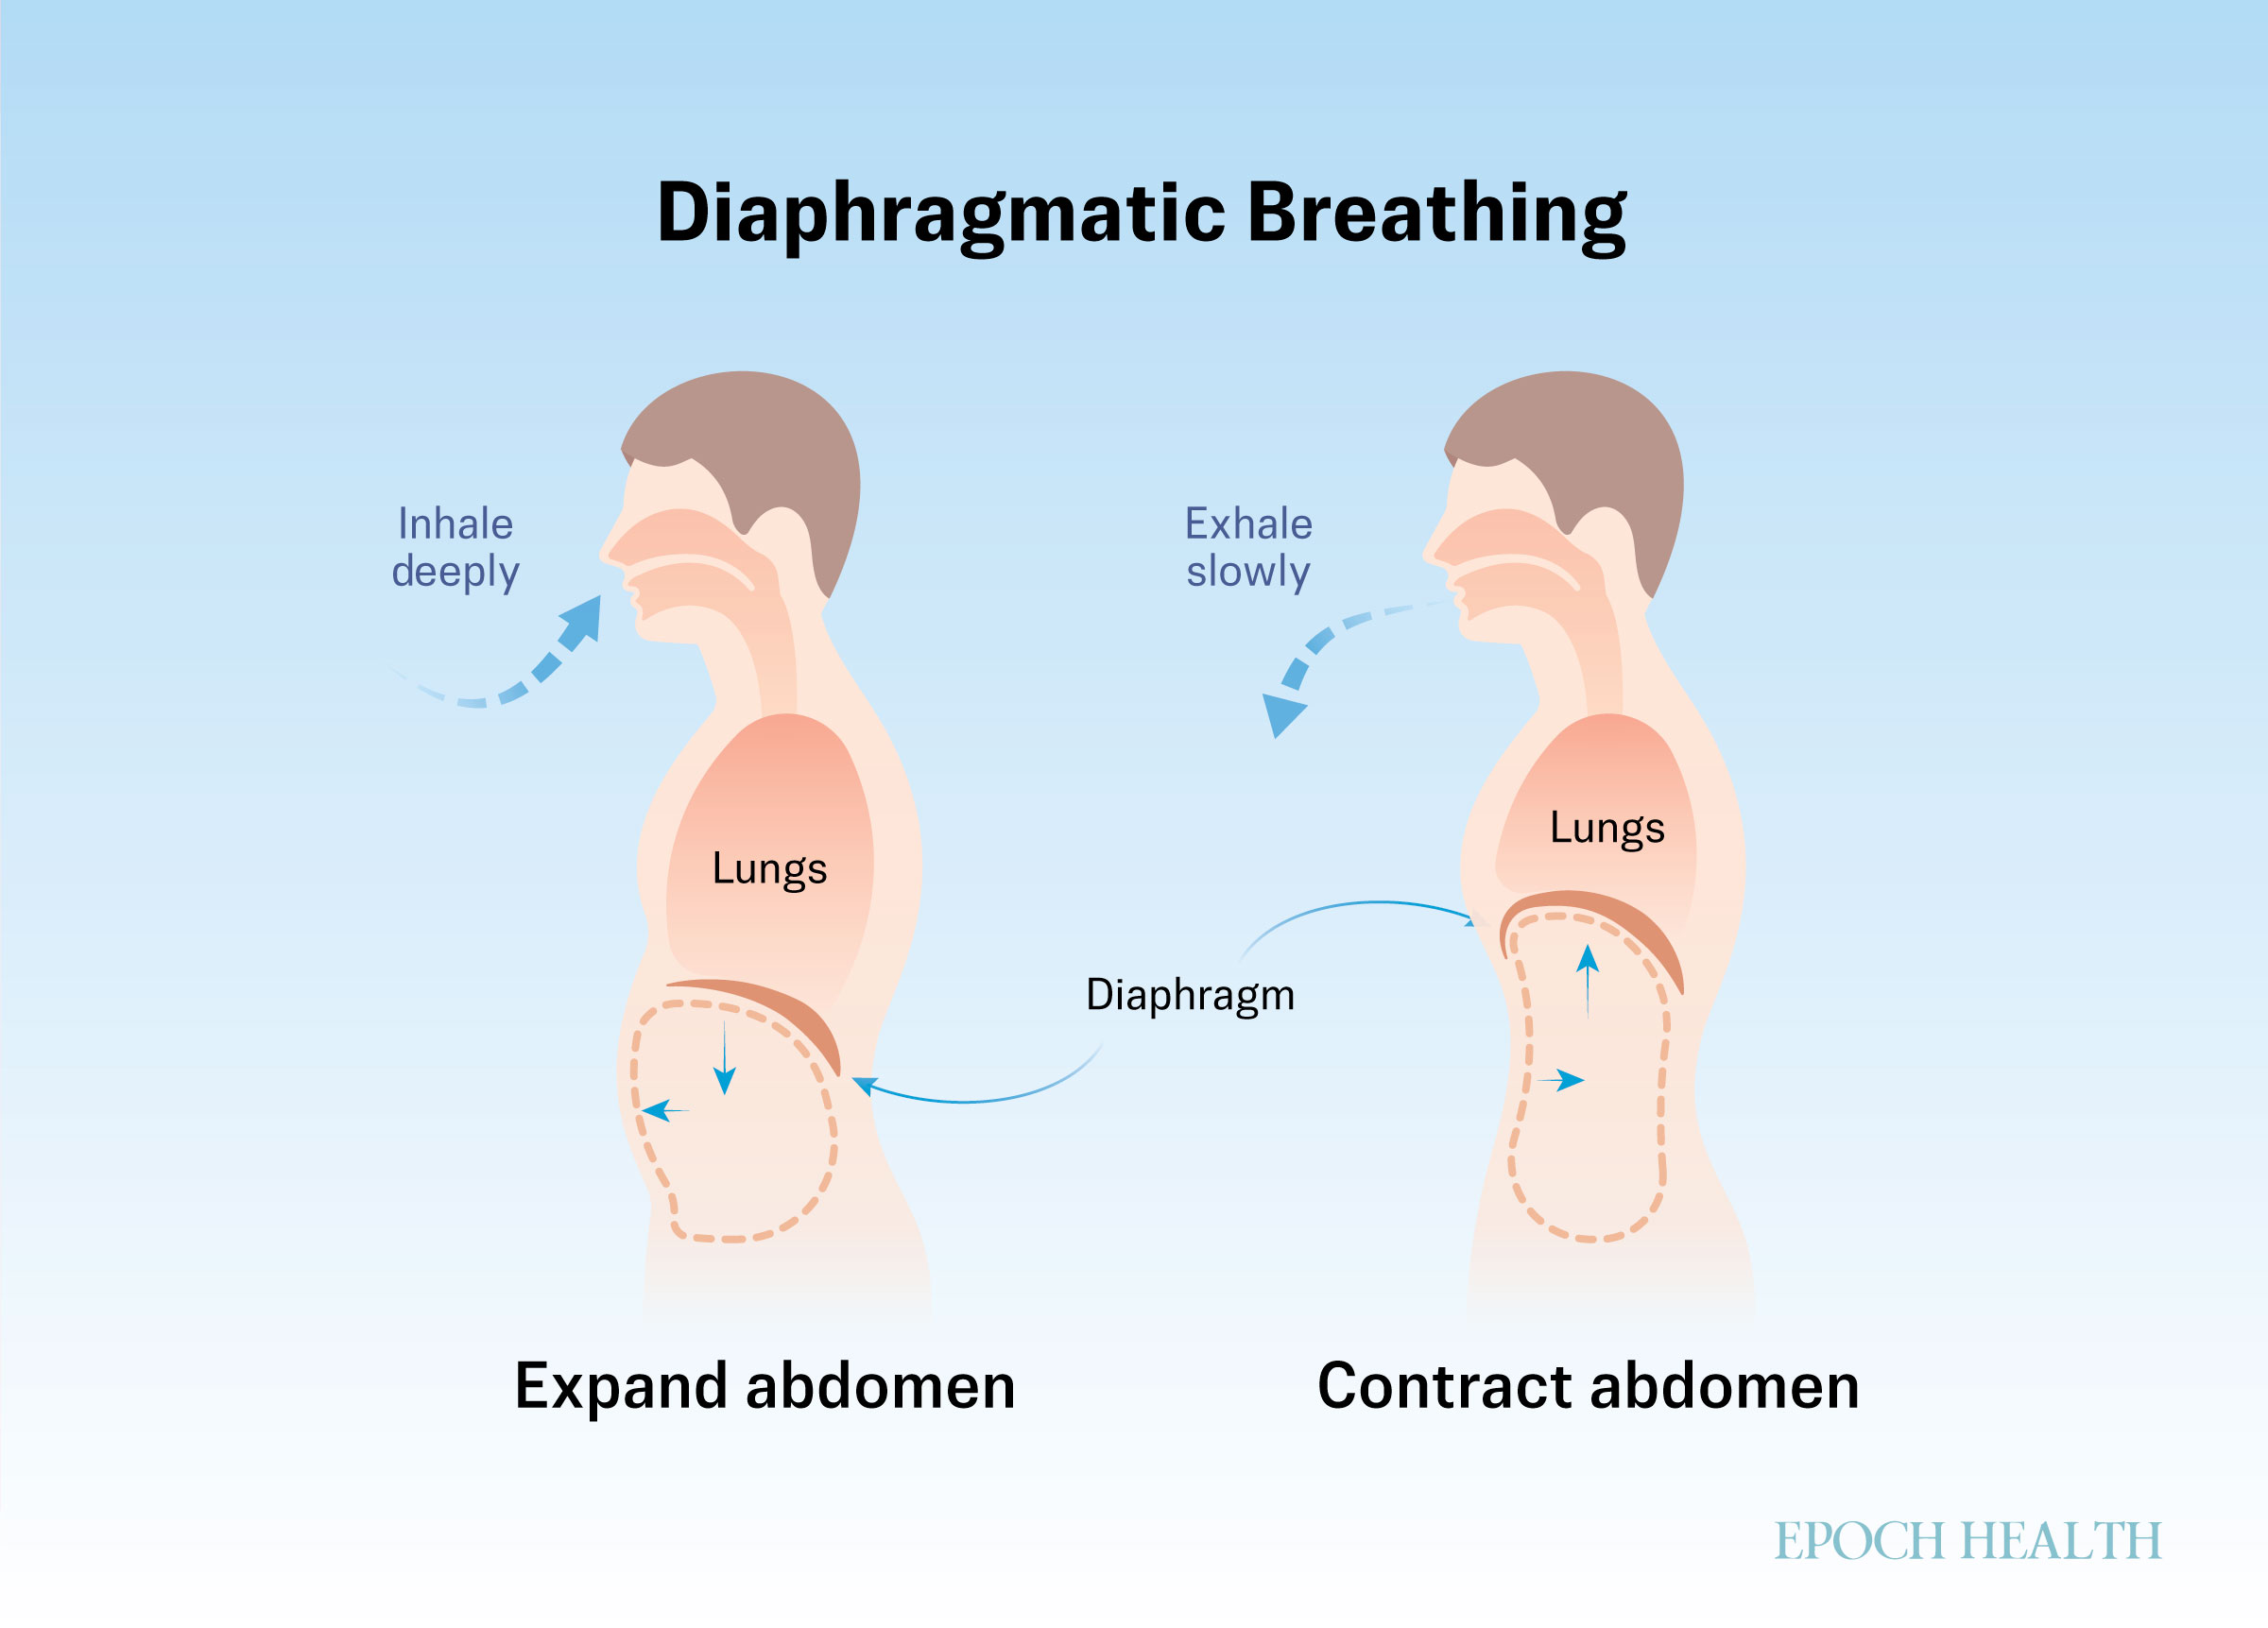

Diaphragmatic breathing, for example, slows the breath, lowers stress hormones, and calms the nervous system. Also known as “belly breathing,” this practice involves the active use of your diaphragm—the large muscle located under your lungs—to draw air deeply into your lungs. As you inhale, your belly rises instead of your chest, allowing more oxygen in and triggering the body’s relaxation response.

- Next 20 Minutes: Abdominal breathing. Inhale deeply through the nose, contract the diaphragm, relax the abdominal muscles, and expand the abdomen. Exhale slowly through your mouth, relax your diaphragm, and contract your abdominal muscles, and pull your abdomen in.